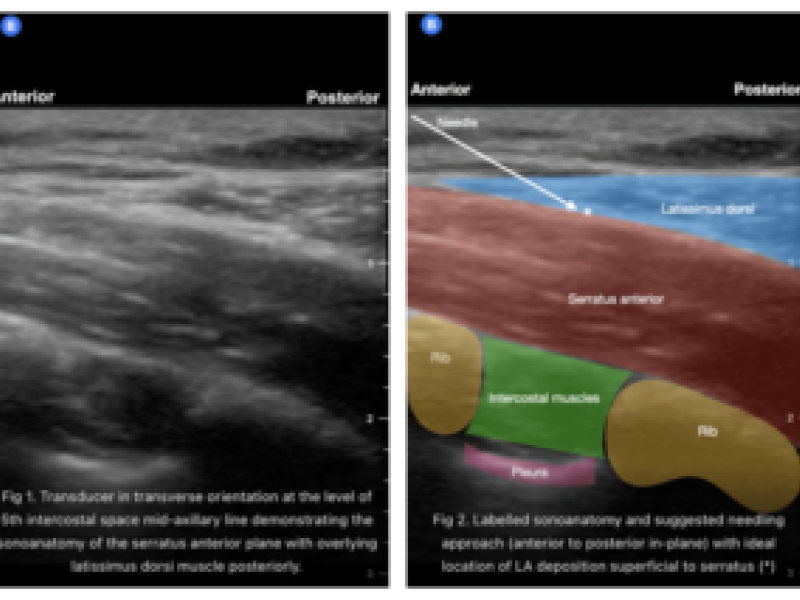

Rib Fractures part 2/Serratus Anterior Nerve Block: By Dr. DeMarzo

Rib fractures can be an incredibly painful condition for